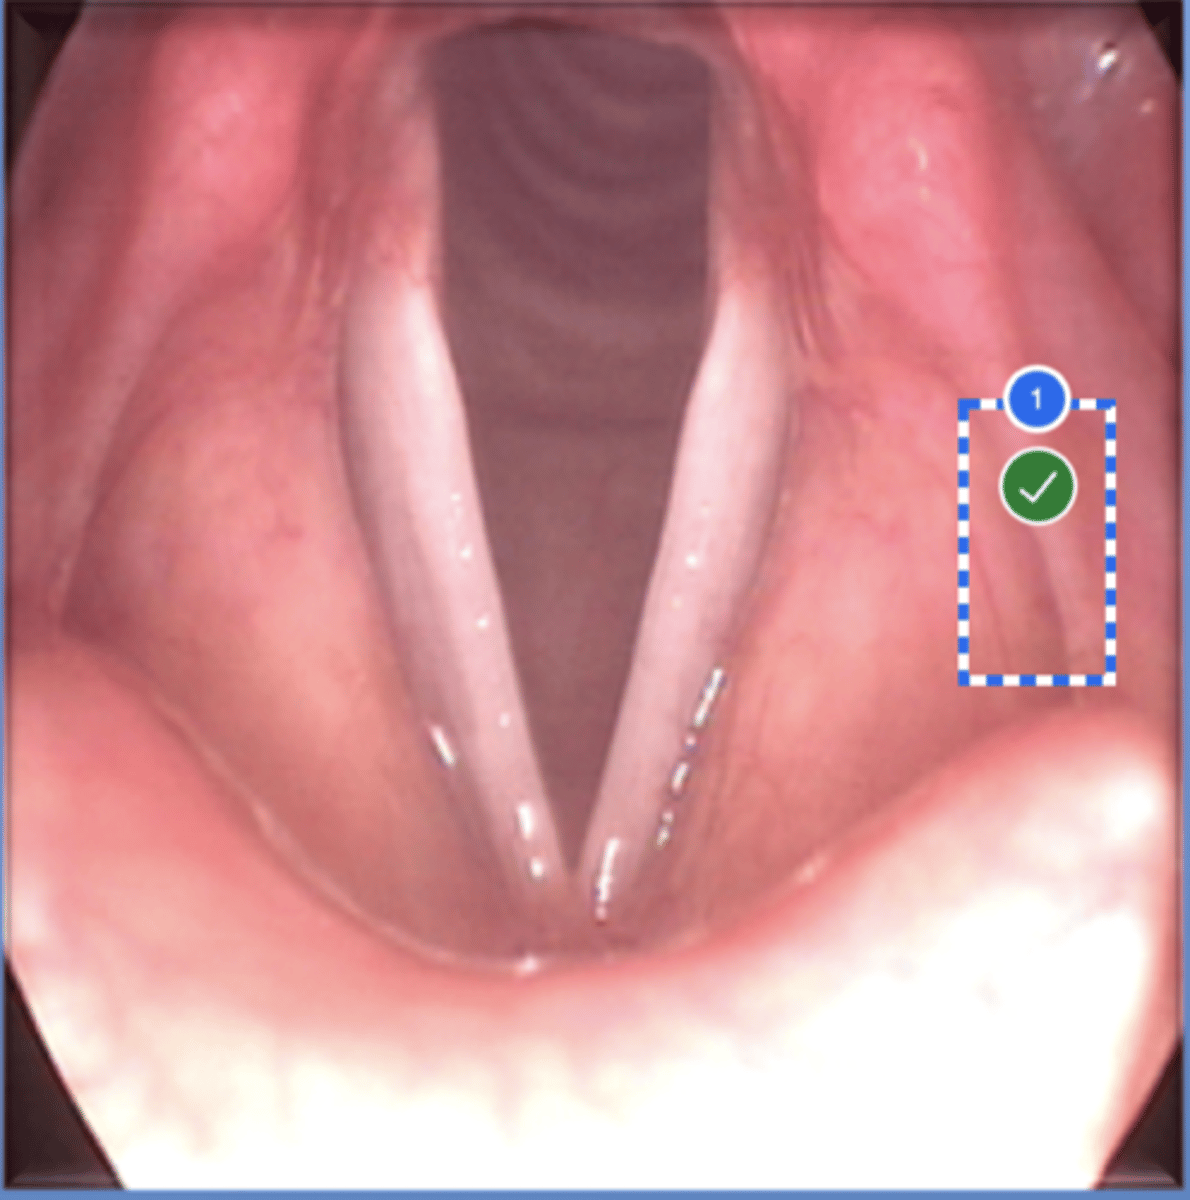

Label left true vocal fold (superior view)

Label right false vocal fold (superior view)

label right arytenoid (superior view)

Label trachea (superior view)

Label epiglottis (superior view)

Label left aryepiglottic fold (superior view)

Label laryngral surface of epiglottis (superior view)

Label lingual surface of epiglottis (superior view)

Label base of tongue (superior view)

Label right pyriform sinus (superior view)

Label upper esophageal sphincter (superior view)

Label right true vf (superior view)